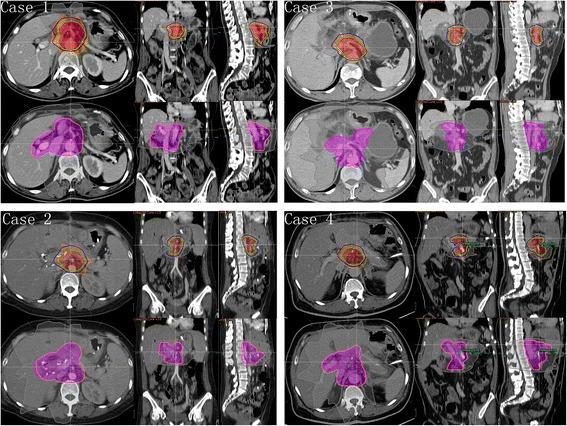

Patients with pancreatic cancer who had undergone surgery for the primary tumor in pancreas at our institution from January 2010 to August 2015 were retrospectively analyzed. All local recurrences were plotted on the computed tomography (CT) image of a representative patient according to their relative coordinates to superior mesenteric artery (SMA) or celiac axis (CA). Adjuvant radiation clinical target volume (CTV)-90 and CTV-80 were created to cover 90 % and 80 % plotted recurrences. This planning approach was applied in four simulated cases with comparison to the plan according to RTOG 0848 contouring consensus guidelines. Raystation v4.5.1.14 was used for analyzing high throughput physics data.

Eighty-three patients with local recurrence were included from 305 postoperative pancreatic cancer patients who did not receive adjuvant radiotherapy. Thirty-one (37 %) patients did not have adjuvant therapy at all, 52 (63 %) patients undergone adjuvant chemotherapy alone. Spatial location of local failure was created. Most recurrences occurred near CA or SMA. CTV-90 was generated through expanding the combined SMA and CA contours by 30 mm right-lateral, 21 mm left-lateral, 20 mm anterior, 13 mm posterior, 10 mm superior, and 20 mm inferior. CTV-80, smaller in volume, was also created for simultaneous integrated boost. Through comparison and analysis of the simulated cases, the radiation volumes proposed were much smaller than those with RTOG 0848 contouring consensus guidelines (average volume: PTV-80 = 120 ml, PTV-90 = 220 ml, RTOG PTV = 490 ml). Accordingly, the organs at risk received less irradiation dose with the proposed CTV-90 and CTV-80.